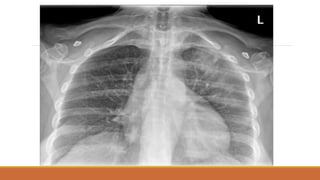

TDMP TỰ DO

PHIM NẰM

MỜ LAN TỎA PHẾ TRƯỜNG VỚI BÓNG MẠCH MÁU VẪN CÒN

MỜ VÙNG ĐỈNH PHỔI VÀ NGOẠI BIÊN

MẤT BÓNG MỜ SẮC NÉT CỦA VÒM HOÀNH ĐỒNG BÊN

TÙ GÓC SƯỜN HOÀNH

DÀY RÃNH LIÊN THÙY BÉ

TDMP TỰ DO PHIMNẰM MỜ LAN TỎA PHẾ TRƯỜNG VỚI BÓNG MẠCH MÁU VẪN CÒN MỜ VÙNG ĐỈNH PHỔI VÀ NGOẠI BIÊN MẤT BÓNG MỜ SẮC NÉT CỦA VÒM HOÀNH ĐỒNG BÊN TÙ GÓC SƯỜN HOÀNH DÀY RÃNH LIÊN THÙY BÉ